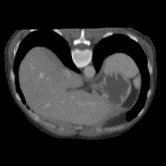

In clinical practice, well-aligned multi-modal images, such as Magnetic Resonance (MR) and Computed Tomography (CT), together can provide complementary information for image-guided therapies. Multi-modal image registration is essential for the accurate alignment of these multi-modal images. However, it remains a very challenging task due to complicated and unknown spatial correspondence between different modalities. In this paper, we propose a novel translation-based unsupervised deformable image registration approach to convert the multi-modal registration problem to a mono-modal one. Specifically, our approach incorporates a discriminator-free translation network to facilitate the training of the registration network and a patchwise contrastive loss to encourage the translation network to preserve object shapes. Furthermore, we propose to replace an adversarial loss, that is widely used in previous multi-modal image registration methods, with a pixel loss in order to integrate the output of translation into the target modality. This leads to an unsupervised method requiring no ground-truth deformation or pairs of aligned images for training. We evaluate four variants of our approach on the public Learn2Reg 2021 datasets \cite{hering2021learn2reg}. The experimental results demonstrate that the proposed architecture achieves state-of-the-art performance. Our code is available at https://github.com/heyblackC/DFMIR.